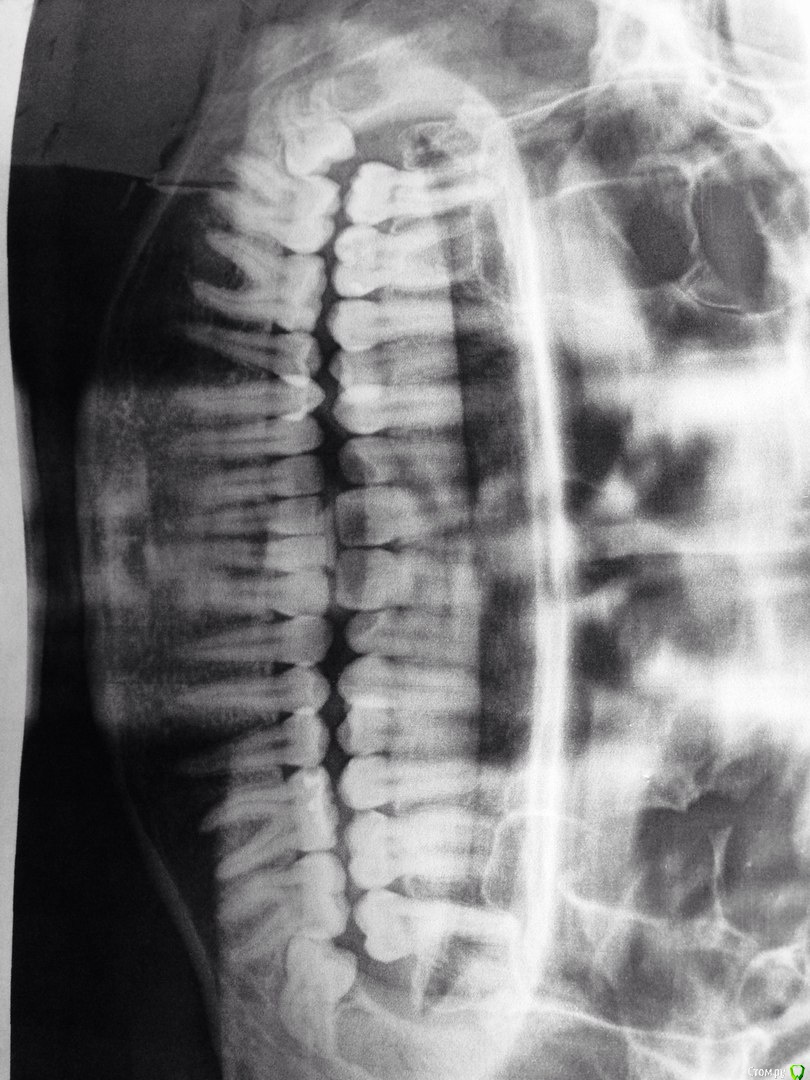

ksu_shine Опубликовано 16 декабря, 2016 Поделиться Опубликовано 16 декабря, 2016 (изменено) Доброго времени суток!Мне 27 лет, два месяца назад ощутила рост коренных нижних с обеих сторон. Сейчас прорезался чуть только правый.На консультации врач сказала: однозначное удаление, со срезанием "капюшона" и выпиливанием зуба по частям. После такой процедуры минимум несколько дней, сказала, буду отходить. Через пару месяцев (не раньше) можно делать второй зуб.Вопрос: если зубы не прорезались и не болят (только мешают из-за уменьшения набухшего пространства во рту), можно ли отложить/забить на удаление? Если удаление показано, то почему? И действительно ли озвученная процедура удаления единственно возможна в данном случае(может есть менее травматичные способы)? Также, слышала, что много осложнений после таких удалений бывает (нескольких знакомых клали в больницы до недели). Может посоветуете обезболивающее для "пережития" следующих дней после удаления..Заранее благодарю за Ваш ответы/совет! Изменено 16 декабря, 2016 пользователем ksu_shine Ссылка на комментарий

Zlata-doctor Опубликовано 17 декабря, 2016 Поделиться Опубликовано 17 декабря, 2016 однозначно удалять, можете потерять семерки ( там очень велика вероятнсть развития кариеса на прилегающих поверхностях). Наверное, в Москве можно найти врача, который обойдется без "больницы". Возможно, оба зуба можно будет удалить одновременно, надо конкретно смотреть врачу 1 Ссылка на комментарий

red_butler Опубликовано 17 декабря, 2016 Поделиться Опубликовано 17 декабря, 2016 Оба удаляйте. Зубы не сложные, если под седацией, то оба за раз. Промедление может сгубить седьмые зубы. Ссылка на комментарий

Bier Опубликовано 17 декабря, 2016 Поделиться Опубликовано 17 декабря, 2016 согласен. Надо удалять оба зуба иначе они испортят 7ки. Ссылка на комментарий